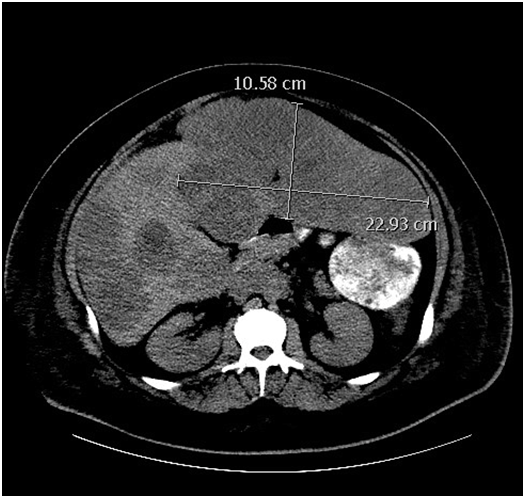

The patient is a 20-year-old male who initially noticed swelling in his scrotum for approximately 3-4 months after being hit with a pellet gun in his groin. He was evaluated by a local physician and treated for epididymitis, but after no improvement in symptoms, he presented to the Emergency Department at an outside hospital with worsening scrotal and abdominal pain. A CT abdomen/pelvis was performed and revealed wide-spread metastatic disease to the liver, lungs, and retroperitoneum (Figure 1A) (Figure 1B). He underwent a testicular ultrasound (U/S), which revealed an enlarged right testicular mass. He subsequently underwent a right-sided orchiectomy and was diagnosed with nonseminomatous testicular cancer (further specifics of pathology were pending at time of initial management). The patient was then discharged home to follow up as an outpatient.

Figure 1 (CT without contrast prior to therapy).